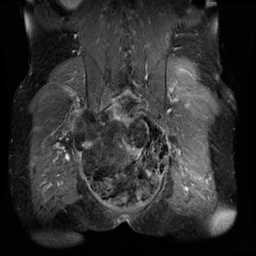

42-year-old male with gradually enlarging left thigh mass. Images demonstrate a multiseptated T1 hyperintense, STIR hypointense, heterogeneously enhancing mass enveloping the left femoral diaphysis and extending into the surrounding soft tissues. No periosteal reaction. There are enhancing, wispy, septations on the postcontrast images with more nodular excrescences at the inferior most aspect of the mass. On resection, this lesion was found to be a well-differentiated liposarcoma, which represents the second most common soft tissue sarcoma. Liposarcoma typically arise in adults between the ages of the 40 and 60 years. Typical locations include the extremities or retroperitoneum. Well-differentiated liposarcoma is the most common subtype, occurring in greater than 50% of cases. Extremity liposarcomas are typically slow growing and have variable rates of localized disease recurrence with deeper lesions more likely to recur. Primary surgical treatment is with wide local excision.